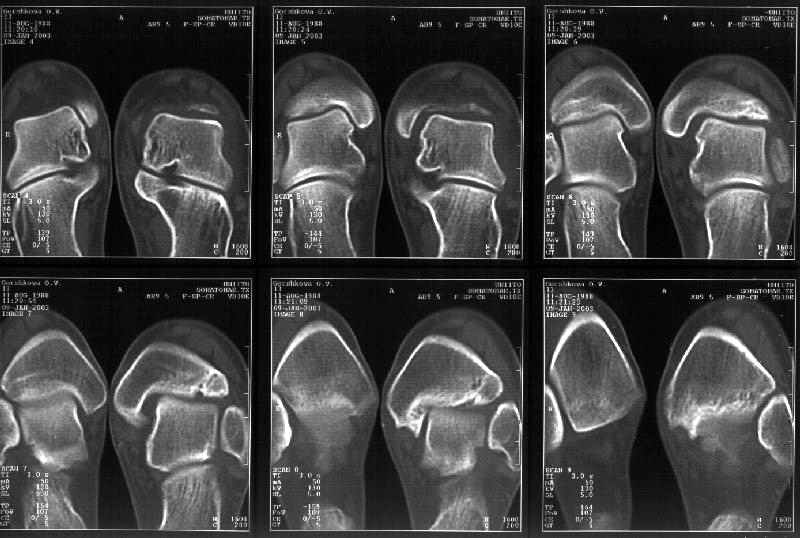

Отправитель: Alexander Chelnokov 19 Январь 2003, 22:34

Сегодня пациентке сделали сравнительную КТ. А ксиальные и Фронтальные срезы приложены. Ваше мнение?

Фронтальные

Аксиальные

Спасибо за КТ -она изумительная. К сожалению, я по дороге на врачебный викенд на Мёртвом море и не смогу подготовить комментарий и схемку до 19.01.03 Помоему, результат КТ даёт чёткую возможность красивой и эффективной помощи.

Отправитель: Й. Воск 19 Январь 2003, 22:50

На КТ я попытался изобразить скромными своими способностями (А)- место перелома, (С)- нормальный суставной зазор меж тараном и тремя его маллеолами. (В)- образовавшийся в результате перелома широкий раза в три зазор, позволяющий, по-моему, сублюксацию тарана при ходьбе. В свете данных КТ, критически важных, я бы предложил вертикальную остеотомию места перелома

задне-внутренним подходом и фиксацию мед. маллеола прижатым к тарану с помощью тонкого compression screw. После этого гипсовый сапожок и немедленное расхаживание ноги.